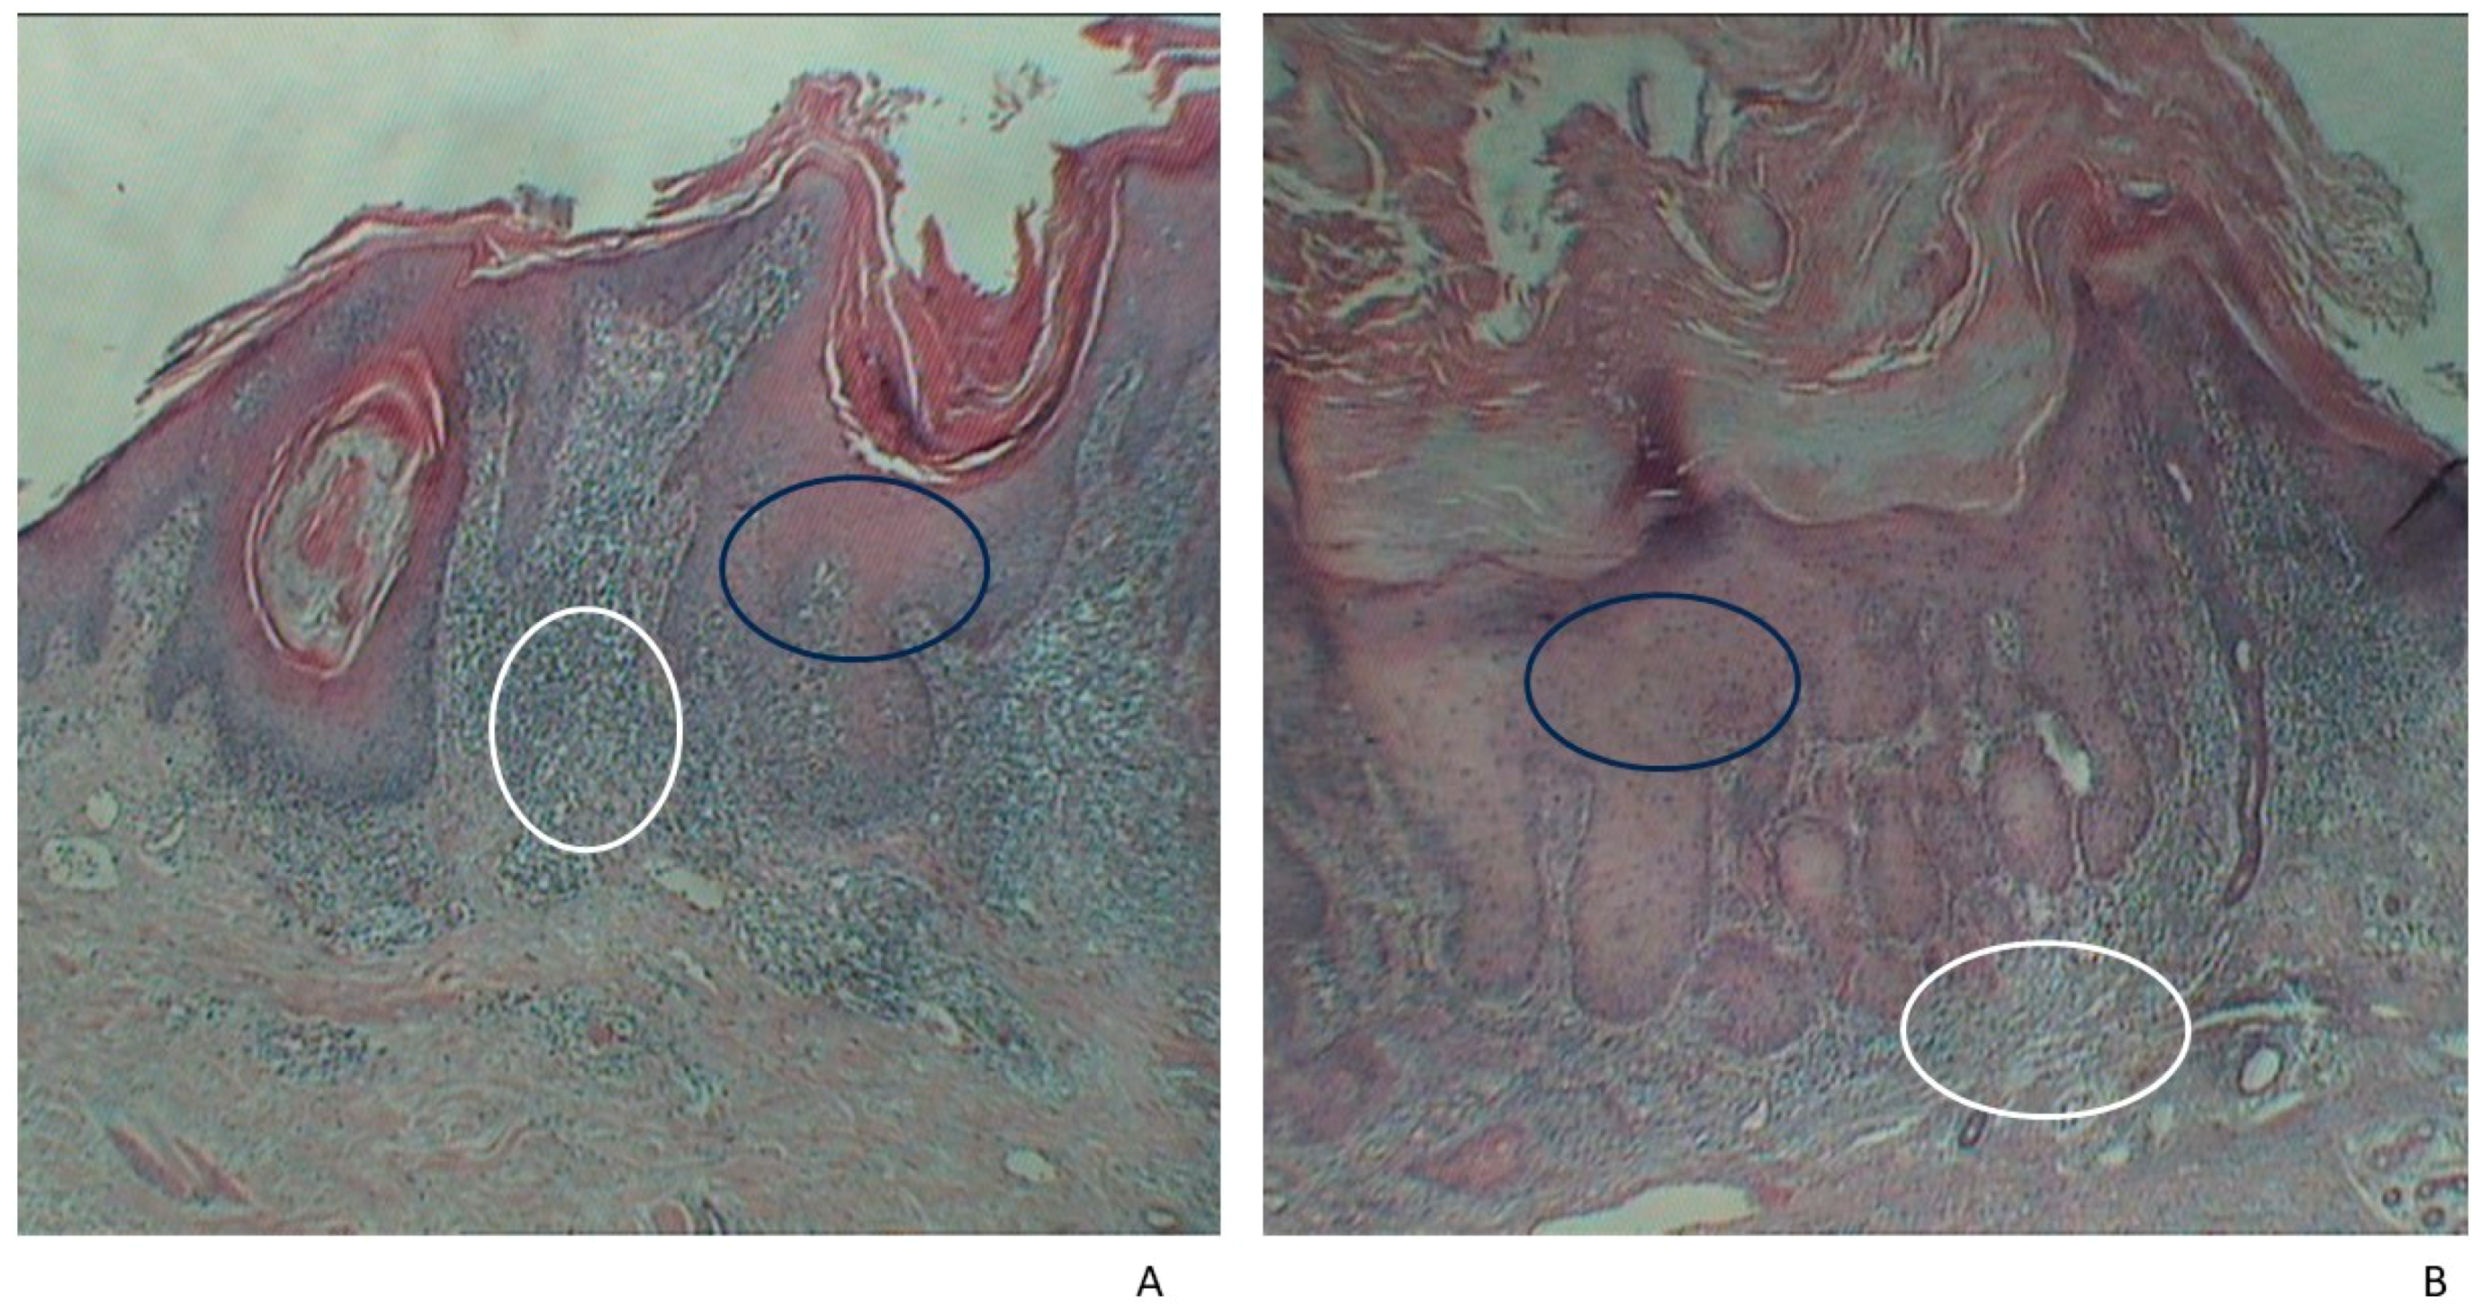

2.2. Histopathological Examination